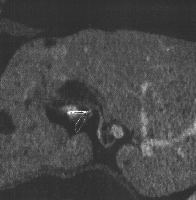

Πρόκειται για άνδρα ασθενή 70 ετών ο οποίος, στα πλαίσια διερεύνησης καθημερινών εμπύρετων επεισοδίων, διαπιστώθηκε ότι έπασχε από πολλαπλά αποστημάτια του αριστερού ηπατικού λοβού, ως συνέπεια ηπατικής λιθίασης (εικόνα 1). Επιπλέον, ο ασθενής παρουσίαζε στένωση στο διχασμό του κοινού ηπατικού πόρου (εικόνα 2) και θρόμβωση του αριστερού κλάδου της πυλαίας φλέβας. Αν και η ύπαρξη κακοήθειας δεν επιβεβαιώθηκε ιστολογικά, η ανάπτυξη χολαγγειοκαρκινώματος δεν μπορούσε να αποκλεισθεί προεγχειρητικά και έτσι ο ασθενής υποβλήθηκε σε εκτομή του χοληδόχου πόρου με λεμφαδενικό καθαρισμό (εικόνα 3) και αριστερή ηπατεκτομή με τον κερκοφόρο λοβό (εικόνα 4). Η αποκατάσταση του χοληφόρου δέντρου πραγματοποιήθηκε με τελικο-τελική ηπατικο-νηστιδική αναστόμωση (εικόνα 5) με τη χρήση οπισθοκολικής έλικας μήκους 70 cm κατά Roux en Y (εικόνα 6). Έκτοτε, ο ασθενής είναι ελεύθερος εμπύρετων επεισοδίων.